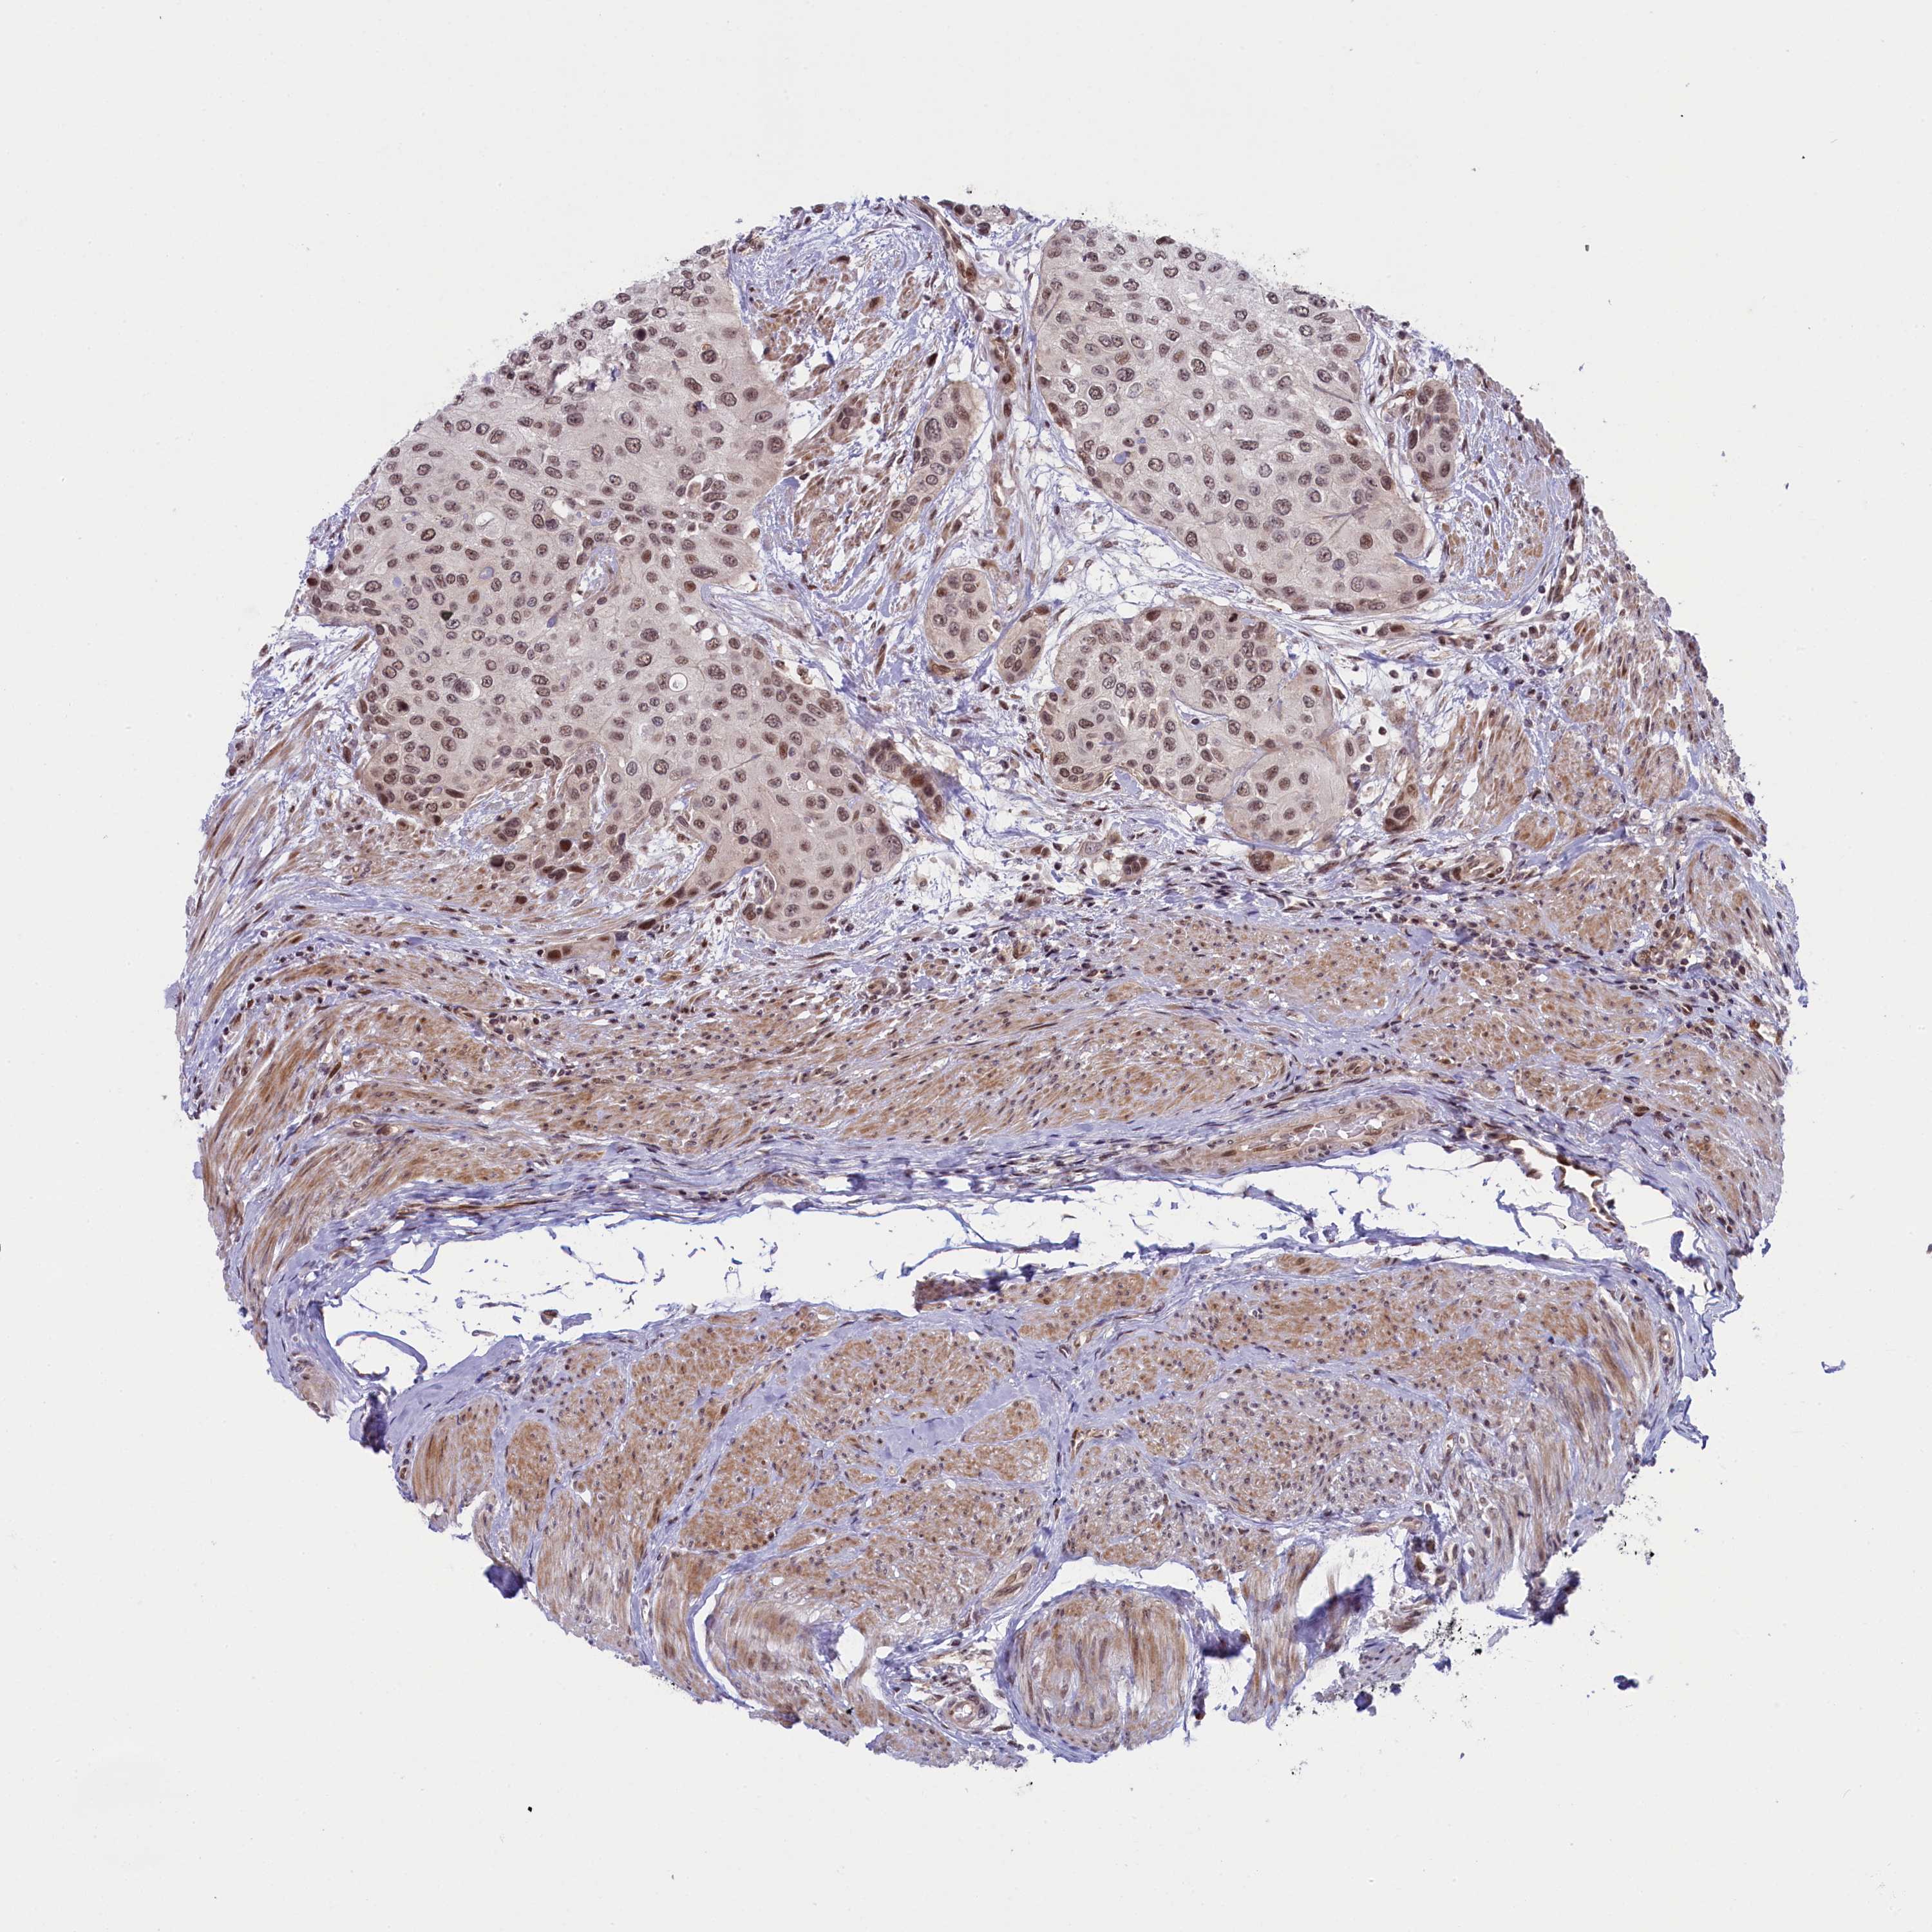

UROTHELIAL CANCER - Protein expressioni

A mouse-over function shows sample information and annotation data. Click on an image to view it in a full screen mode. Samples can be filtered based on level of antibody staining by selecting one or several of the following categories: high, medium, low and not detected. The assay and annotation is described here.

Antibody stainingi

Antibody staining in the annotated cell types in the current human tissue is reported as not detected, low, medium, or high, based on conventional immunohistochemistry profiling in selected tissues. This score is based on the combination of the staining intensity and fraction of stained cells.

Each image is clickable and will lead to virtual microscopy that enables deeper exploration of all samples and also displays staining intensity scores, fraction scores and subcellular localization as well as patient and tissue information for each sample.

Antibody HPA041653

Staining

High

Medium

Low

Not detected

Intensity

Strong

Moderate

Weak

Negative

Quantity

>75%

75%-25%

<25%

None

Location

Nuclear

Cytoplasmic/membranous

Cytoplasmic/membranous,nuclear

Urothelial carcinoma, High grade

Urothelial carcinoma, Low grade